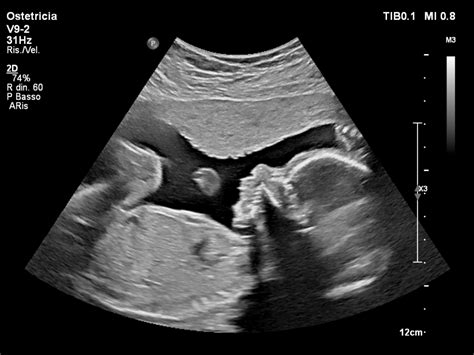

La scelta di sottoporsi a screening prenatali come l'Ultrascreen o la translucenza nucale (TN) è spesso motivata dalla volontà di avere una visione più completa dello sviluppo del feto. In alcuni casi, come quello di una delle testimoni, un "sesto senso" o una sensazione di inquietudine hanno portato a prendere precauzioni inaspettate, come lasciare il figlio maggiore a casa dei nonni prima di un'ecografia. Questo presagio, sebbene non immediatamente comprensibile, si è rivelato premonitore di notizie difficili.

Quando durante un'ecografia la plica nucale risulta alterata e la percentuale di rischio di anomalie aumenta significativamente (ad esempio, 1/5), la realtà può crollare in un istante. Le parole del medico, che comunica una situazione "non delle migliori" e la possibile presenza di anomalie a livello degli organi, creano un clima di profonda angoscia. La domanda inevitabile: "È down?" può essere seguita da risposte ancora più sconvolgenti, come la possibile presenza di anomalie più gravi o incompatibili con la vita.